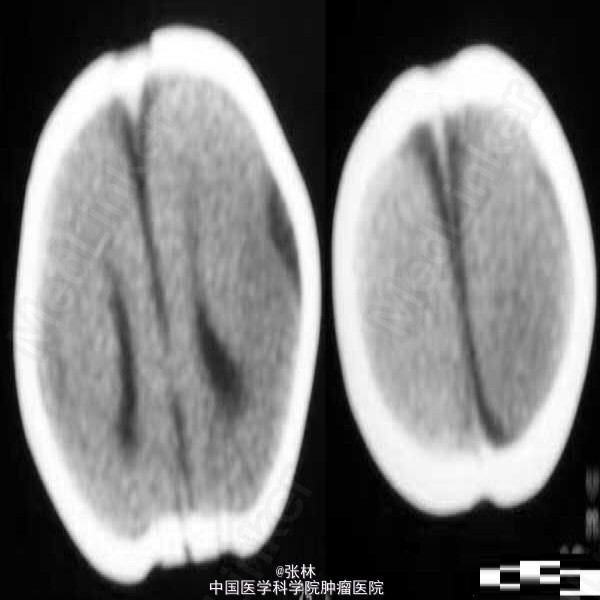

【临床病史】:患儿,F/0.5Y。癫痫,近一个月来频发。五官尚可,头颅大小与同龄儿相比稍小,智力低下(平时家人逗小孩时目光及动作迟缓)。 【影像表现】:显示双侧大脑半球皮层明显增厚、表面光滑、无脑回及脑沟,皮层下白质稀少。双侧外侧裂变浅、凹陷,整个双侧大脑半球呈“8”字形表现,脑室系统扩大。前纵裂增宽、增深,与第三脑室向连通。双侧侧脑室扩大、分离。 【影像诊断】:无脑回畸形伴胼胝体发育不良(Lissencephaly associated with Corpus Callosum dysplasia) 【诊断要点】:无脑回畸形伴胼胝体发育不良 【讨论】:无脑回畸形和/或巨脑回畸形:无脑回畸形指大脑表面光滑,无脑回结构;巨脑回畸形指大脑停留在原始阶段,脑回宽、扁。两者仅为畸形成度不同,可同时存在于脑的不同部位。前者多在顶枕部,后者多位于额部。镜下管前者大脑皮质结构异常,皮质分层不完全或不分层,常见不成熟的神经细胞。后者皮层保留了原始皮层的4曾神经细胞结构,神经细胞分化不成熟。白质中常发现异位的神经细胞,有时呈结节状。 [临床表现] 无脑回畸形患儿在新生儿期常有小头畸形和轻微面部异常,以后表现出智力落后。完全性无脑回畸形者大多在2岁前死亡。巨脑回存活者常有智力低下和癫痫。 [CT表现] 无脑回畸形和/或巨脑回畸形,前者主要表现为脑表面光滑,脑回、脑沟消失,皮层增厚,白质减少。后者主要表现为侧裂变浅、增宽,脑回增宽,皮质增后,内表面光滑,白质减少,患侧脑室系统扩大。此外,无脑回畸形两侧裂变浅,呈“8”字形表现。